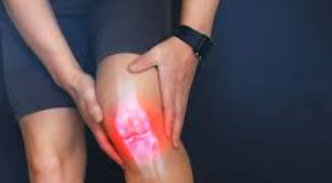

무릎 연골 손상의 가장 대표적인 증상은 무릎 관절 부위의 통증입니다. 초기에는 운동 후나 장시간 활동 후에만 나타나지만, 손상이 진행되면서 일상적인 움직임에서도 통증이 발생합니다. 특히 계단을 오르내리거나 쪼그려 앉는 동작에서 통증이 심화되는 특징을 보입니다.

연골 손상으로 인한 통증은 날카로운 찌르는 듯한 통증보다는 둔하고 깊은 곳에서 느껴지는 통증의 양상을 보입니다. 무릎을 직접 눌렀을 때 압통이 느껴지며, 특히 무릎뼈 주변과 관절선 부위에서 압통이 두드러집니다.

통증과 압통